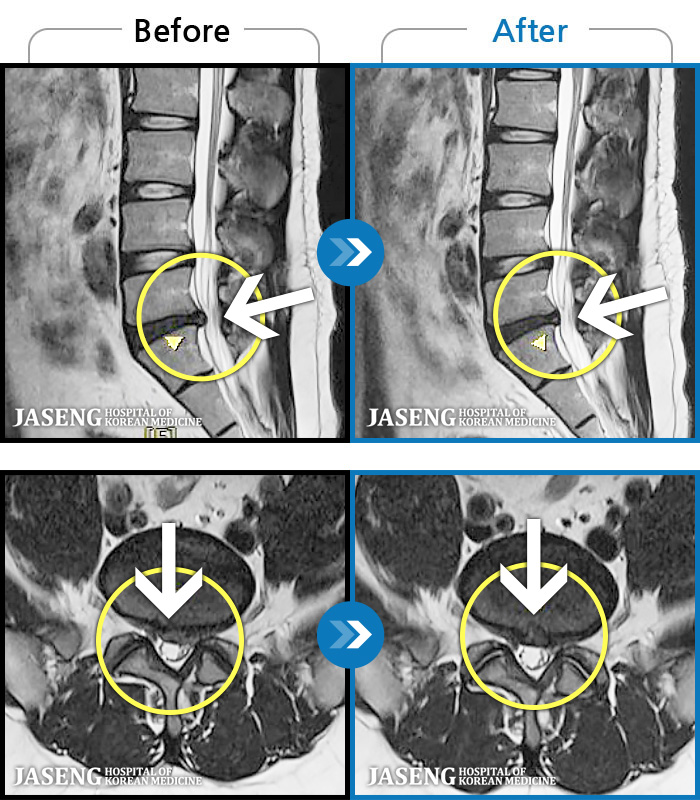

- MRI ġ

MRI ġ

1,237 MRI ũ ʸ Ȯϼ.